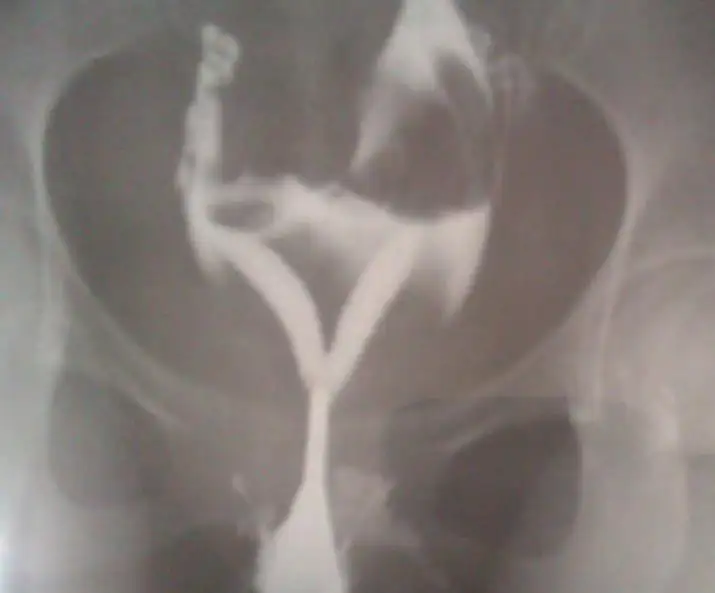

merhaba arkadaşlar.ben aranıza yeni katıldım. ben 2,5 yıllık evliyim. 2 yıldır bebek istiyorduk ve sonunda geçen ay hamile kaldım fakat 5 haftalık bir gebelik sonucu düşük yaşadım malesef. doktor muayenede rahimimim çift olduğunu ve rahimde perde olduğunu ayrıca rahimimin ters olduğunu söyledi.ve rahim filmi istedi.bu hafta rahim filmini çektirdik.fakat rahim emarı da istiyor doktorum onu da haftaya çektireceğim. şimdi resimlerini yüklüyorum rahim filmimin.sizce rahimde perde mi var yoksa rahim çift mi ? internetten araştırdım şekline bakılırsa ''Uterus bicornis'' gibi geliyor bana. daha doktorum bieşy demedi.emarı da görüp öyle söyleyecekmiş.sizce nedir? çift rahim mi yoksa rahimde perde mi ????

sağol canım teşekkür ederim.tüpler açıkmış şükürler olsun . ama işte o Y harfi gibi görünen perde mi yoksa çift rahim mi işte o çok önemli benim için. inş perdedir diyorum dua ediyorum artık. perde ise çözüm kolay çünkü.ufak bir operasyonla perdeyi alabiliyorlarmiş.

emar sonuçlarımı da dün aldım. malesef ki çift rahim dedi doktorum. histereskopi ye gerek yok emar da gayet belli dedi. uterus bicornis imiş benim durumum. yani tek giriş ama sonradan ikiye ayrılıyo Y gibi aynen. ve ameliyat pek yapılmıyormuş bu duruma. doktorum da zaten kesinlikle ameliyat önermiyorum dedi. tek yapacağımız hamile kaldığında düşük olmaması için elimizden geleni yapmak dedi. böyle işte. malesef üzgünüm.çünkü düşük ihtimalim çok çok yüksek olacak.

arkadaşım öncelikle geçmiş olsun diyorum. ve kendi yaşadıklarımdan yola çıkarak sana başka doktorlara da gitmeni tavsiye ediyorum.bende 29 yaşındayım. yaklaşık 2 yıl önce bebek düşünmeye başladığımızda önce doktora gittim.tabi eşimde gitti sperm tahlili filan yaptırdı.bende bir rahatsızlığım varsa önce tedavi olayım ki vakit kaybetmeyeyim dedim. gittim muayene oldum tahlil filan verdim. doktor bana hiçbir şeyin yok herşeyin normal , stres yapma zamanla hamile kalırsın dedi. bende 2 yıl bekledim herşeyim normalde stresten olmuyo herhalde dedim.geçen ay hamile kaldım ve hamile olduğumu öğrendikten 1 hafta sonra yani 5 haftalık iken gebeliğim düşükle sona erdi. bu sefer kardeşiminde gittiği doktora gideyim dedim. doktor ilk muayene de o an söyledi . sende ya çift rahim var yada rahimde perde var dedi. hemen rahim filmi yani HSG istedi. o hafta rahim filmi çekildim. gene tam net anlaşılmadı bu sefer rahim emarı istedi doktorum. çünkü histereskopi biraz daha zor bişey dedi.şimdi boşu boşuna delik açmayalım göbeğine dedi. emar da sonuçsuz kalırsa son çare histereskopi yaparız dedi. bir de histereskopi pahalı da bişey. boşuna dünyanın parasını verme dedi.neyse rahim emarı da çekildim. sonuç olarak çift rahim çıktı. benimkinin ismi ''uterus bicornis'' yani çift boynuzlu rahim. benim tüpler açıkmış yumurtalar normalmiş fakat işte çift rahim.aynı Y harfi gibi görünüyor rahim filminde. hatta fotosunu bir iki sayfa öncesine yüklemiştim bakabilirsin. yani diyeceğim o ki ; bir doktor yüzünden tam 2 yıl kaybettim. herşeyim normal sandım. meğerse hiç de öyle değilmiş. tek doktorla kalma konusunda çok iyi doktorlara git derim. yaş da 29 olunca fazla vakit kaybetmemek gerekiyor mecburen. benim doktorum bana hamile kalabileceğimi ve doğum yapabileceğimi söyledi.normal hamilelerden tek farkın ilk 3 ay düşük riskin yüksek olacak ve yatmak zorunda kalabilirsin dedi.3.cü ayında rahimine dikiş atarız böylece erken doğumu engellemeye çalışırız dedi. normal rahimlilere göre rahimin yarım sayılır fakat millet ikiz doğuruyor sende tek doğurursun nolcak yani bişey olmaz dedi. tabi ben aynı film ve emar sonuçlarını uzman başka doktorlara da götürdüm onlarda aynı teşhisi koydu. bence önce bir emar çektir derim. hiç olmazsa histereskopi yapılır. biraz uzun yazdım k.bakma lüften.